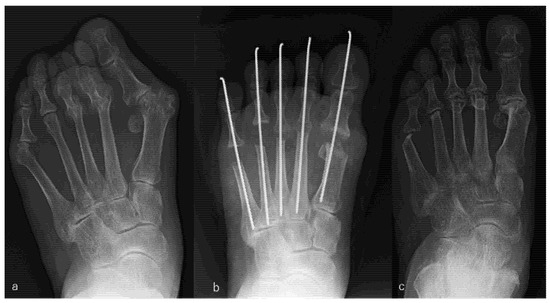

Resection arthroplasty for the big and lesser toes was performed in the same way as that described for the PR group, and soft tissue repair was performed as that described for the PP group. An example is shown in Figure 3.

Figure 3.

Rheumatoid arthritis (RA) in a 56-year-old woman. Metatarsophalangeal joint resection arthroplasty for the big and lesser toes was performed. RA had been present for 26 years. The patient received etanercept (50 mg/week), methotrexate (8 mg/week), and prednisolone (3 mg/day). Radiographic views of her left foot before surgery (a), immediately after surgery (b), and 9 years after surgery, which was the latest follow-up (c). Scores on the Japanese Society for Surgery of the Foot RA foot and ankle scale improved from 38 points before surgery to 79 points at the 9-year follow-up. The mean hallux valgus angle improved from 48° before surgery to 4° immediately after surgery and was 23° at the 9-year follow-up. The patient was satisfied with the clinical results at the 9-year follow-up, although the correction of the hallux valgus angle had decreased slightly and the metatarsal bone had shortened compared with the values immediately after surgery.